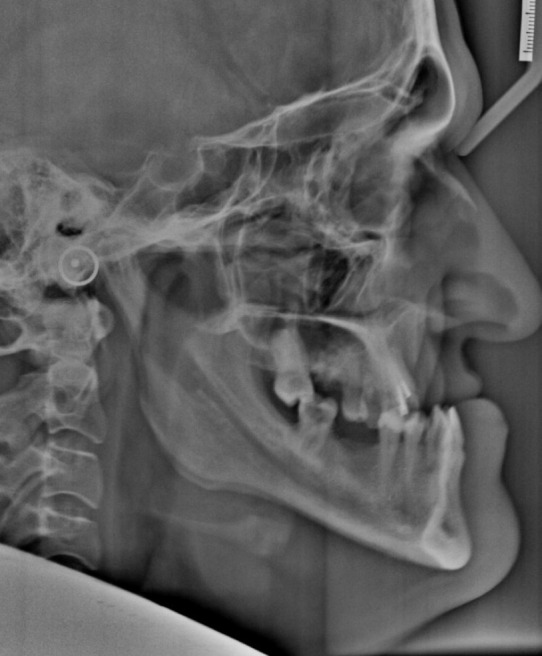

正颌手术是治疗面部美学和咬合问题患者的关键治疗方法,传统上包括术前正畸,手术和术后正畸治疗。然而,常规方法持续时间的延长往往导致患者的不满。作为回应,手术优先的方法(SFA)已经成为一种替代方案,旨在简化治疗并减少复杂性。本病例报告探讨了SFA在术前不进行正畸的情况下的实施,重点是其与上颌间固定(IMF)螺钉的整合。一个25岁的男性表现为严重的下颌后颌和面部不对称。放射学评估证实了骨骼差异,促使手术解决。利用三维规划软件,对LeFort I型上颌前进截骨术和双侧矢状劈开截骨术进行了规划。术中策略性放置IMF螺钉以稳定上颌骨下颌复合体。立即矫正术后调整-启动牙列对齐和水平。定期随访,确保治疗进展及稳定。在手术优先入路中使用IMF螺钉有助于精确的手术动作,加快治疗时间,并提高患者舒适度。这种辅助技术代表了一个有前途的途径,以提高手术精度和病人的结果,在正颌手术。需要进一步的研究来探索这种方法在不同患者群体中的长期稳定性和更广泛的适用性。

Orthognathic surgery, a pivotal treatment for patients with significant facial aesthetic and occlusal concerns, traditionally involves a phased approach comprising preoperative orthodontics, surgery, and postoperative orthodontic treatment. However, the extended duration of conventional methods often leads to patient dissatisfaction. In response, the surgery-first approach (SFA) has emerged as an alternative, aiming to streamline treatment and reduce complexity. This case report explores the implementation of the SFA without preoperative orthodontics, focusing on its integration with intermaxillary fixation (IMF) screws. A 25-year-old male presented with severe mandibular retrognathia and facial asymmetry. The radiographic evaluation confirmed the skeletal discrepancy, prompting a surgical solution. Utilizing three-dimensional (3D) planning software, LeFort I osteotomy for maxillary advancement and bilateral sagittal split osteotomy (BSSO) for mandibular setback was planned. IMF screws were strategically placed to stabilize the maxillomandibular complex intraoperatively. Immediate postoperative orthodontic adjustments-initiated dentition alignment and leveling. Regular follow-up ensured treatment progress and stability. The use of IMF screws in the surgery-first approach facilitated precise surgical movements, accelerated treatment timelines, and enhanced patient comfort. This adjunctive technique represents a promising avenue for improving surgical precision and patient outcomes in orthognathic surgery. Further research is warranted to explore the long-term stability and broader applicability of this approach across diverse patient populations.